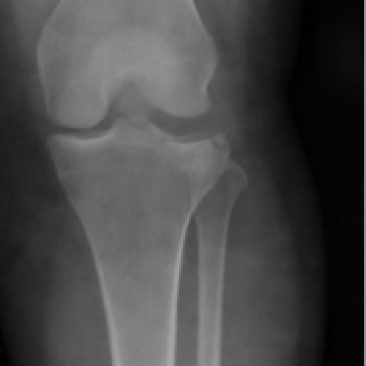

What’s the diagnosis? Gepost op 31 augustus 202027 augustus 2020 door netwerkvsseh What’s the diagnosis? By Dr. Sandhya Ashokumar @emdaily.cooperhealth.org Dit delen: Delen op X (Opent in een nieuw venster) X Share op Facebook (Opent in een nieuw venster) Facebook Delen op LinkedIn (Opent in een nieuw venster) LinkedIn E-mail een link naar een vriend (Opent in een nieuw venster) E-mail Afdrukken (Opent in een nieuw venster) Print Vind-ik-leuk Aan het laden... Gerelateerd